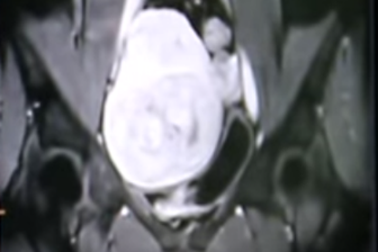

Làm xẹp khối u xơ tử cung lành tính bằng sóng siêu âmNữ bệnh nhân 44 tuổi đã thoát khỏi nguy cơ phải cắt bỏ tử cung sau khi được điều trị bằng sóng siêu âm hội tụ làm nóng và tiêu diệt khối u khổng lồ lành tính.